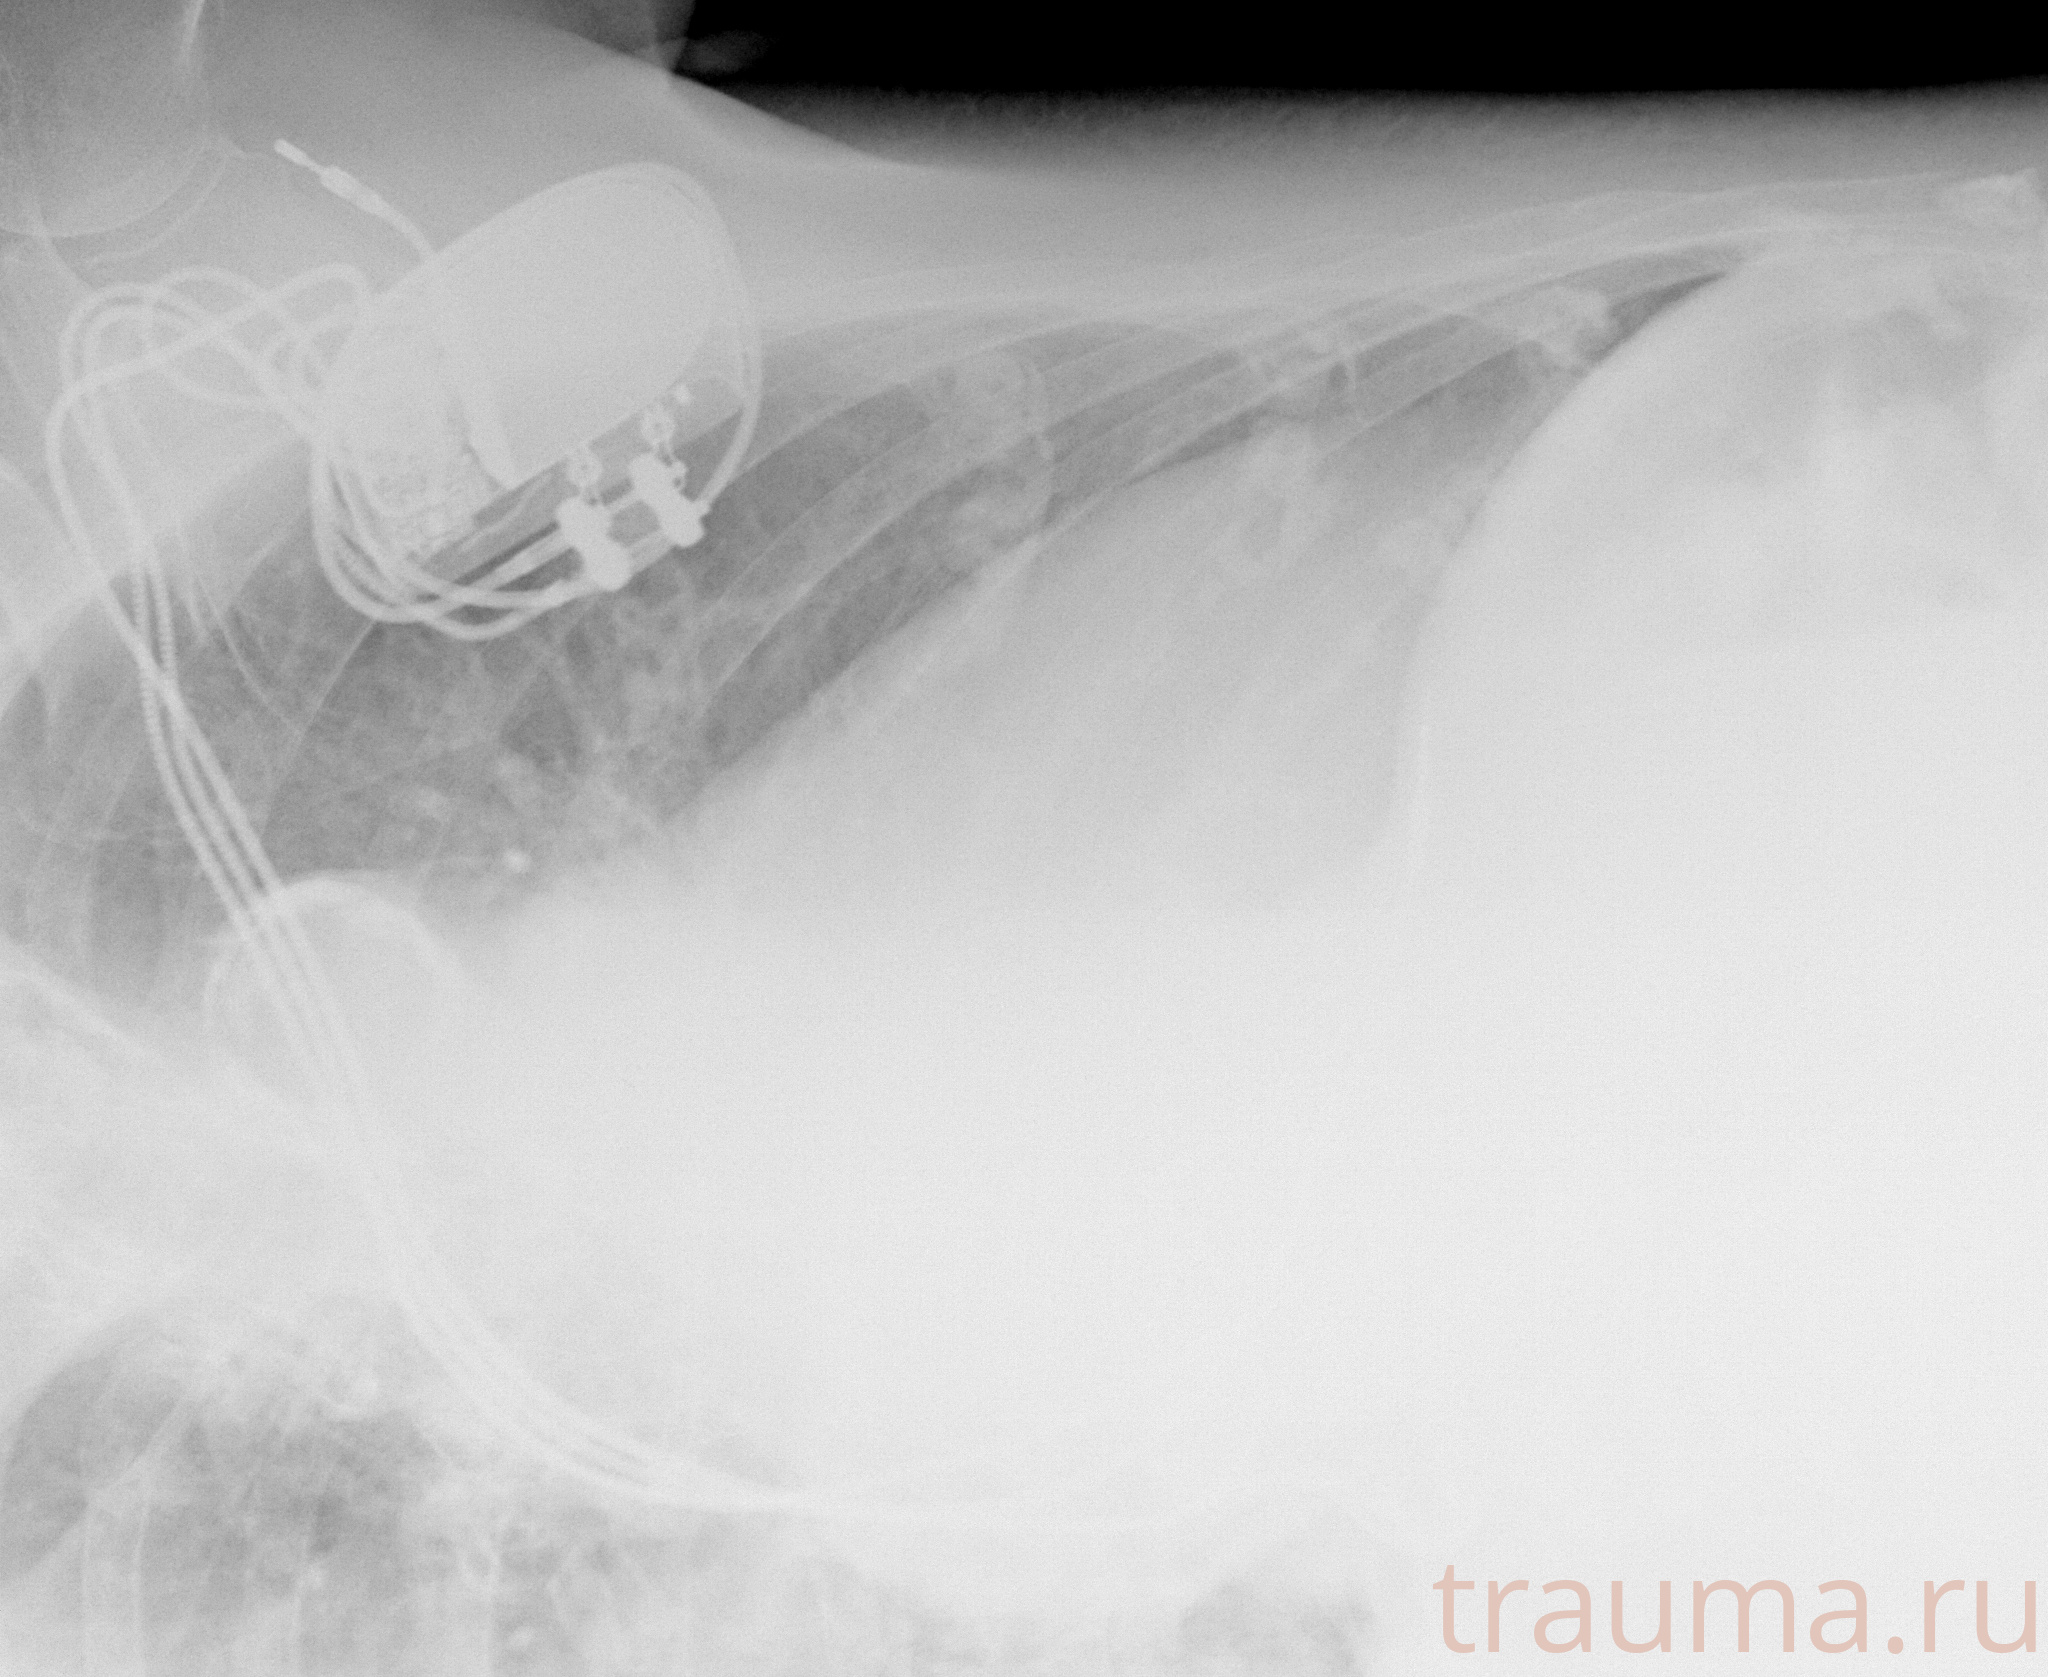

Рентгенограммы

Рентген на дому: по вашему адресу приезжает врач-рентгенолог, травматолог-ортопед с мобильным рентгеновским аппаратом, проводит диагностику травмы или заболевания, делает необходимые рентгенограммы, дает рекомендации по дальнейшему лечению. Получить качественные снимки в домашних условиях возможно благодаря уникальной методике, разработанной МосРентген Центром для института  Склифосовского